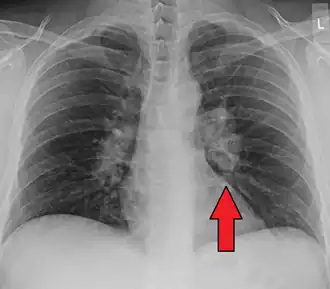

![]() | |

| Chest X-ray showing the typical nodularity of sarcoidosis, predominantly in the hila of the lungs. | |

Chest radiograph changes are divided into four stages:[104]

- bihilar lymphadenopathy

- bihilar lymphadenopathy and reticulonodular infiltrates

- bilateral pulmonary infiltrates

- fibrocystic sarcoidosis typically with upward hilar retraction, cystic and bullous changes